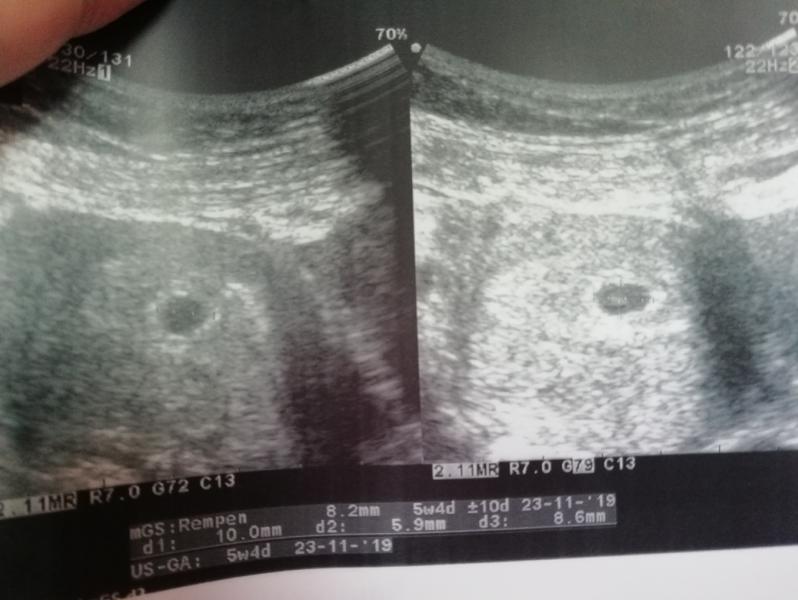

Всем привет!!! Срок по месячным 6.5, на Узи сказали 5.4, плодное яйцо 8.2 мм, но оно пустое, ничего не нашли!!! Не знаю уже что и думать?? У кого такое было, как дальше обстояли дела????

Кто разбирается в УЗИ? Что там светлое справа??

Переделать УЗИ через неделю. Раньше 6-7 недель увидеть эмбрион невозможно, если подтвердиться на повторном УЗИ то сделают чистку.

@viki-pinsk, я ходила в 5-6 недель по месячным, в заключении поставили, что по факту это 3-4. Посмотрели только сам факт наличия беременности. Узист так и сказала, что на таком сроке другого как бы так и быть не должно и ничего не увидеть. Не говоря уже про сердцебиение

У меня на первом УЗИ, как сейчас помню, плодное яйцо было 10мм, это всё, что сказали на тот момент. Сердце не прослушивалось ещё. Через 2 недельки уже всё было :)